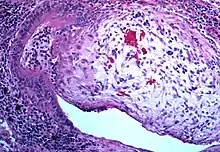

-bronchiolitis_obliterans_(4734022020).jpg)

Obliterative bronchiolitis is often diagnosed based on the symptoms of obstructive lung disease following lung injury. The definitive diagnosis is through biopsy, but due to the variable distribution of lesions, leading to falsely negative tests, and invasive nature of this procedure it is often not performed.[6][11] Several tests are often needed to diagnose obliterative bronchiolitis, including spirometry, diffusing capacity of the lung tests (DLCO), lung volume tests, chest X-rays, high-resolution CT (HRCT), and lung biopsy.[11][4]

Lung biopsy

Transthoracic lung biopsies are preferable for diagnosis of constrictive BO compared to transbronchial biopsies; regardless of the type of biopsy, a diagnosis may only be achieved by examination of multiple samples.[30] Transthoracic biopsies are preferred over transbronchial due to the heterogeneity and distribution of the lesions.[11] OB can be further classified into two categories: constrictive or proliferative.[11] The constrictive pattern is demonstrated by peribronchiolar cellular infiltrates which eventually causes small airway damage and leads to subepithelial fibrosis.[11] The bronchial muscle can eventually become fibrosed which can be identified with trichrome staining.[11] In regards to proliferative disease, intraluminal buds called "Masson bodies" fill the lumen, which results in bronchiolar plugging.[11] Often people with proliferative disease will show butterfly wing-like appearance under microscopy.[11] One key determinate that can be seen on biopsy to differentiate constrictive from proliferative disease is the extent of lesions. Both lesions are localized from the small bronchi to the membranous bronchi, but in constrictive disease the lesions are intermittent while proliferative disease has a continuous distribution.[11]